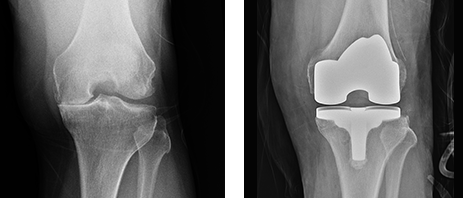

방사선 검사 (X-ray)

방사선 검사를 통해 무릎 관절 뼈와 뼈 사이의 정도를 확인하여 연골의 손실정도를 파악합니다.

[1기]

연골이 조금 손상된 정도로 관절간격 이상 없음. 시술 및 수술은 필요없는 상태

[2기]

연골이 닳기 시작하고 관절간격이 조금 좁아져있음. 일부 시술 필요

[3기]

연골이 많이 닳고 관절간격이 상당히 좁아져 있음. 시술 및 수술 필요

[4기]

연골이 소실되어 있고, 관절자체가 붙어 변형이 생김. 인공관절 수술 필요